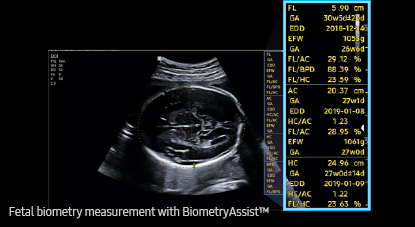

AI BiometryAssist

Una medición semiautomática de los parámetros de biometría fetal

BiometryAssist, la tecnología semiautomática para la medición biométrica, permite a los usuarios medir el crecimiento del feto con mayor rapidez y precisión mientras se mantiene la coherencia del estudio.

más